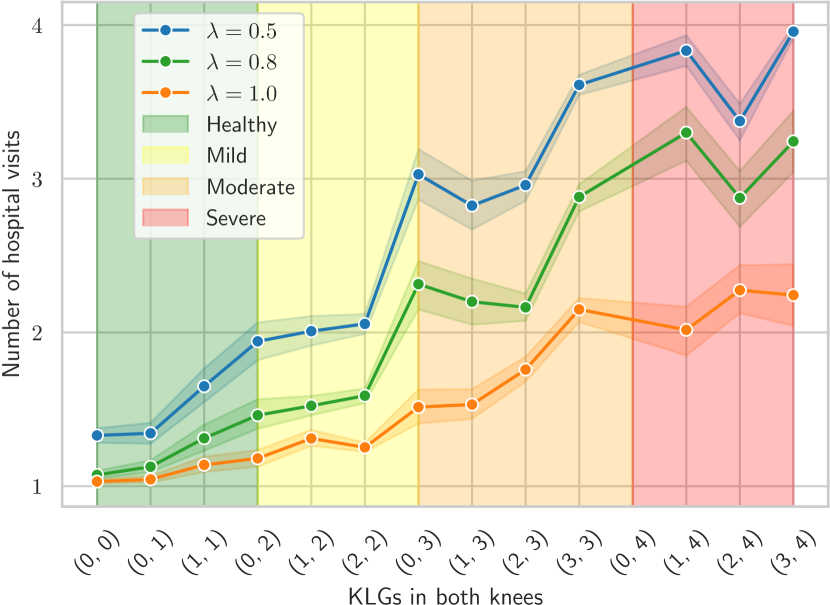

In this section, we assessed the dependency between the number of follow-up decisions made by our method and the disease characteristics. Specifically, Figure 8 visualizes the number of hospital visits per person according to individual KLG pairs measured at the baseline visit (see Suppl. Table S3 for raw data). Those KLG pairs are classified into subgroups, denoted by color regions: ”Healthy” when neither knee has KLG greater than 1, ”Mild” when neither knee has KLG greater than 2, ”Moderate” when neither knee has KLG greater than 3, and ”Severe” when at least one knee has KLG 4. We illustrated our policies with different of , , and by three lines in the graphs. All these policies delivered at least one follow-up to participants regardless of the costs. The diagram shows that our policy learned to be severity-aware, and realized that patients with more severe forms of OA in both knees progress faster. That is, the agent recommended more visits in such a case, and consistently in all considered cost settings.

| Baseline KLGs | Polices | ||

| (0, 0) | 1.33 0.18 | 1.07 0.10 | 1.03 0.06 |

| (0, 1) | 1.34 0.20 | 1.13 0.11 | 1.04 0.07 |

| (1, 1) | 1.65 0.29 | 1.31 0.22 | 1.14 0.13 |

| (0, 2) | 1.94 0.32 | 1.46 0.26 | 1.18 0.15 |

| (1, 2) | 2.01 0.33 | 1.52 0.23 | 1.31 0.18 |

| (2, 2) | 2.06 0.33 | 1.59 0.24 | 1.25 0.16 |

| (0, 3) | 3.03 0.31 | 2.31 0.30 | 1.51 0.20 |

| (1, 3) | 2.83 0.32 | 2.20 0.30 | 1.53 0.20 |

| (2, 3) | 2.96 0.32 | 2.16 0.29 | 1.76 0.26 |

| (3, 3) | 3.61 0.21 | 2.88 0.28 | 2.15 0.25 |

| (1, 4) | 3.83 0.12 | 3.30 0.23 | 2.02 0.21 |

| (2, 4) | 3.38 0.17 | 2.88 0.25 | 2.28 0.23 |

| (3, 4) | 3.96 0.06 | 3.24 0.28 | 2.24 0.27 |